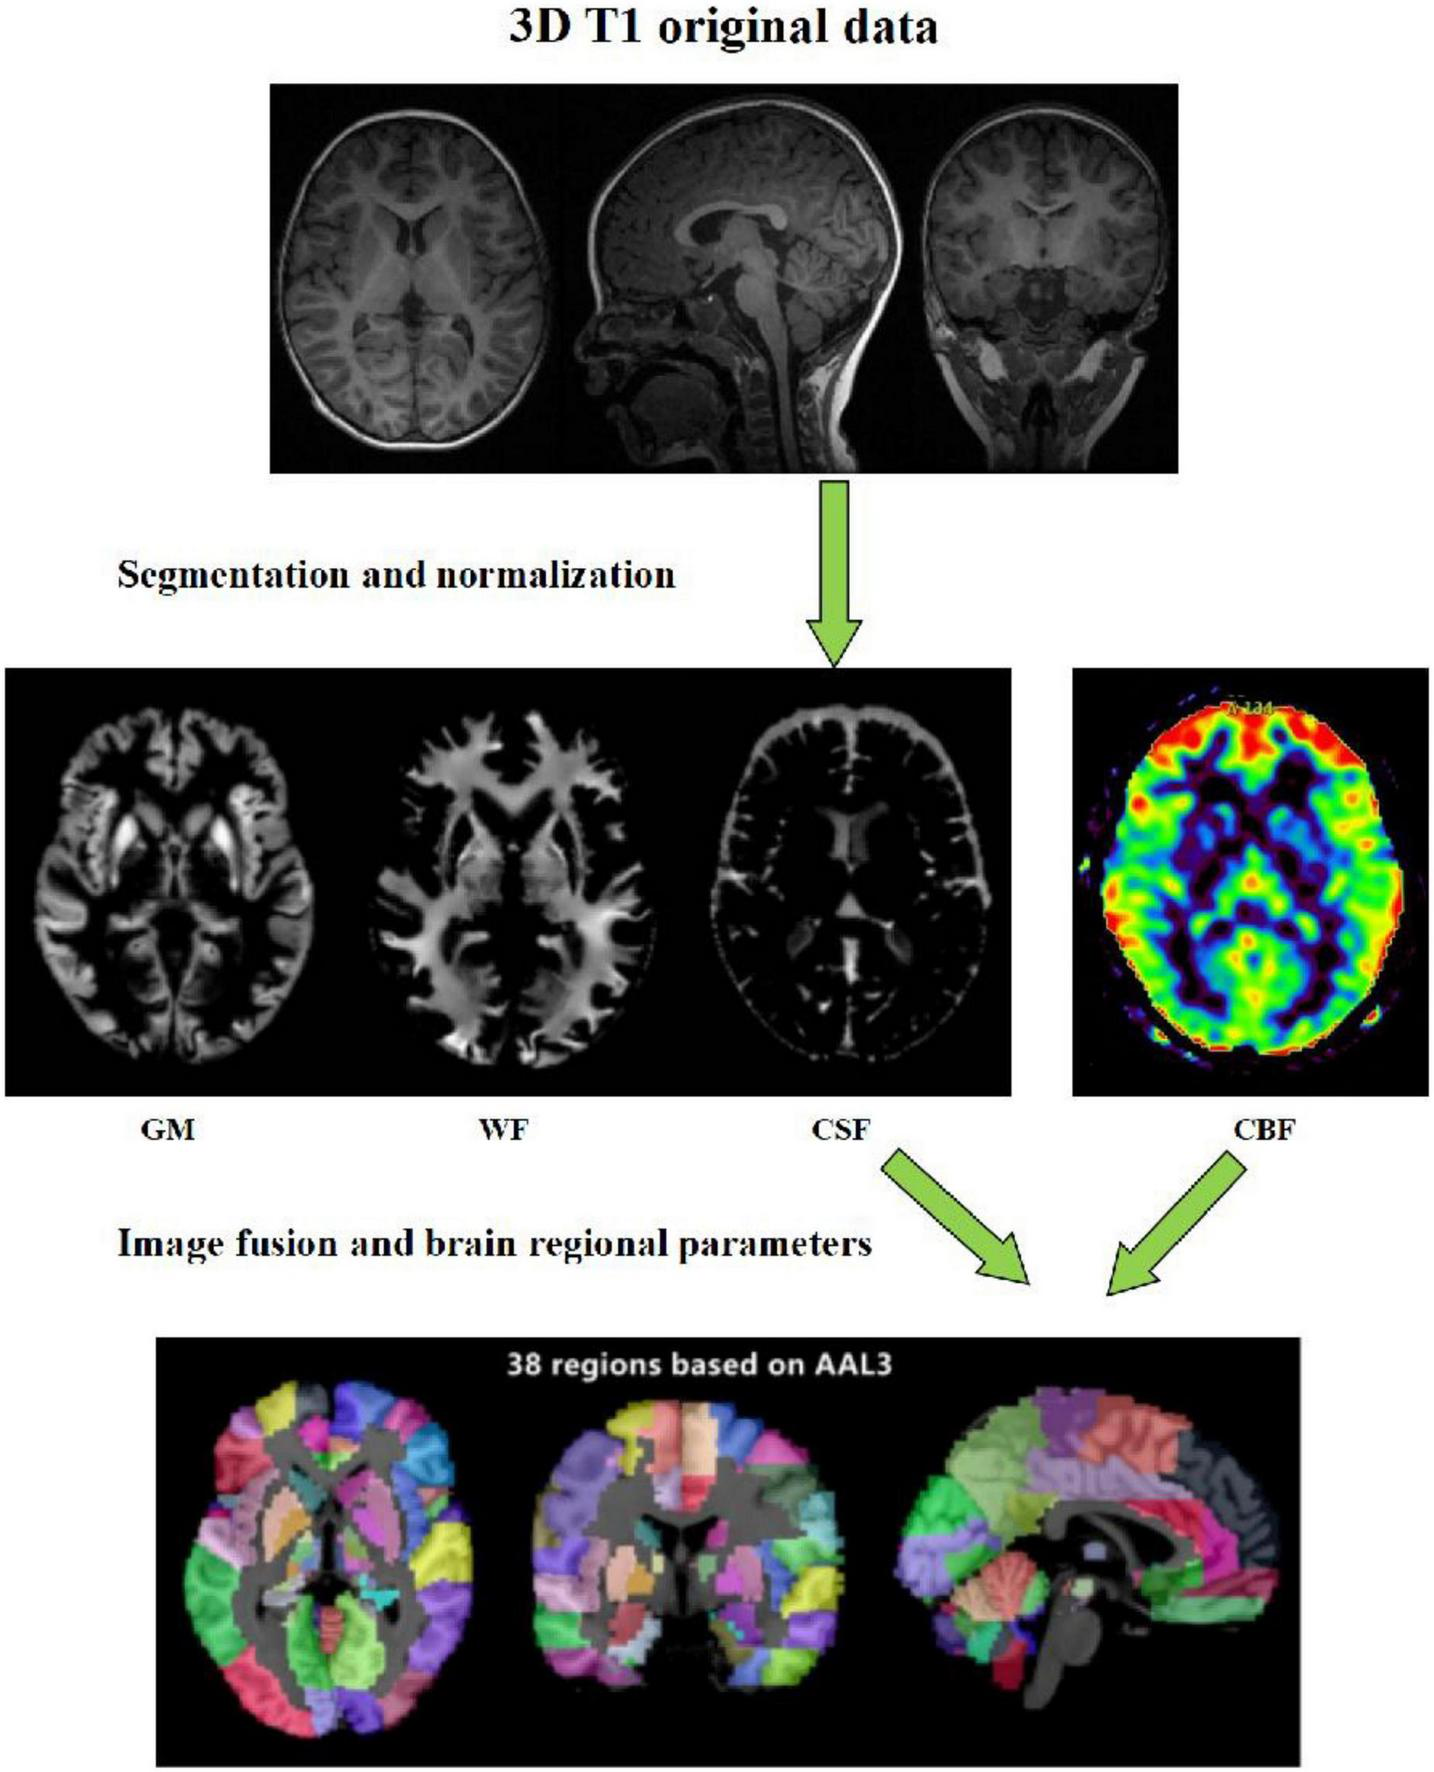

Data analysis: The raw data of 3D-pcASL sequences were imported into Functools software using GE ADW 4.6 workstation to obtain the CBF quantitative maps. In order to calculate the values of volumes, CBF and other quantitative parameters in different brain regions, we used the voxel-based morphometry (VBM) method. On the platform of MATLAB 2018a, we used SPM12 software to register the 3D-T1 sequence structure diagram with CBF quantitative maps, and used CAT12 toolkit to segment the registered CBF structure quantitative maps in SPM12 software, and finally extracted the parameter values of volume and CBF in each brain region (Figure 1).

FIGURE 1

Schematic diagram of the image processing and parameter extraction.